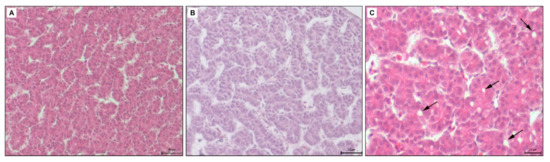

3.2.1. Light Microscopy